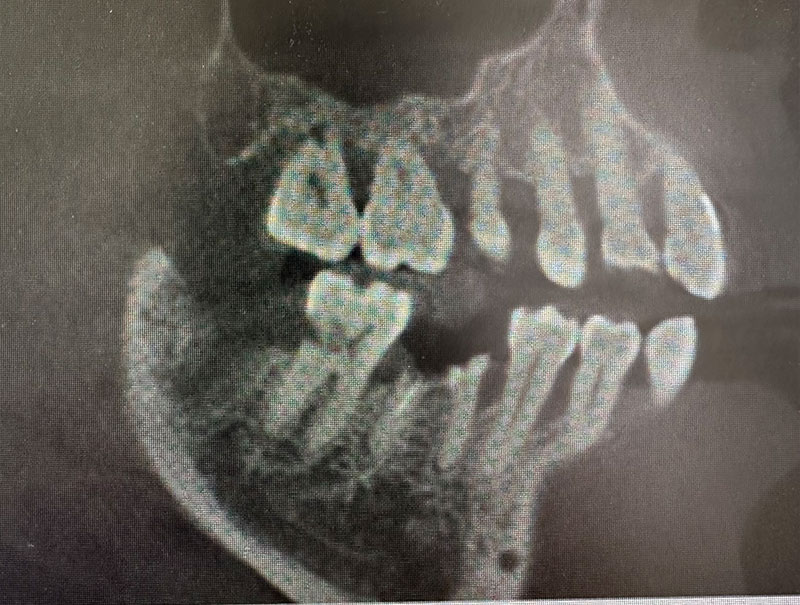

レントゲン写真およびCT画像なのですが、右上6が残歯状態であり歯根破折を起こしている状態でした。しかし歯槽骨から上顎洞底までの距離は十分に認められます。この歯槽骨から上顎洞までの距離がないとソケットリフトなどのオプションの処置が必要になってくるのですが、今回の症例では大掛かりな処置の必要はなく症例の難易度としては比較的イージーな方でした。上顎洞などに関して知りたい方はこちらのページを参照にしていただければと思います。